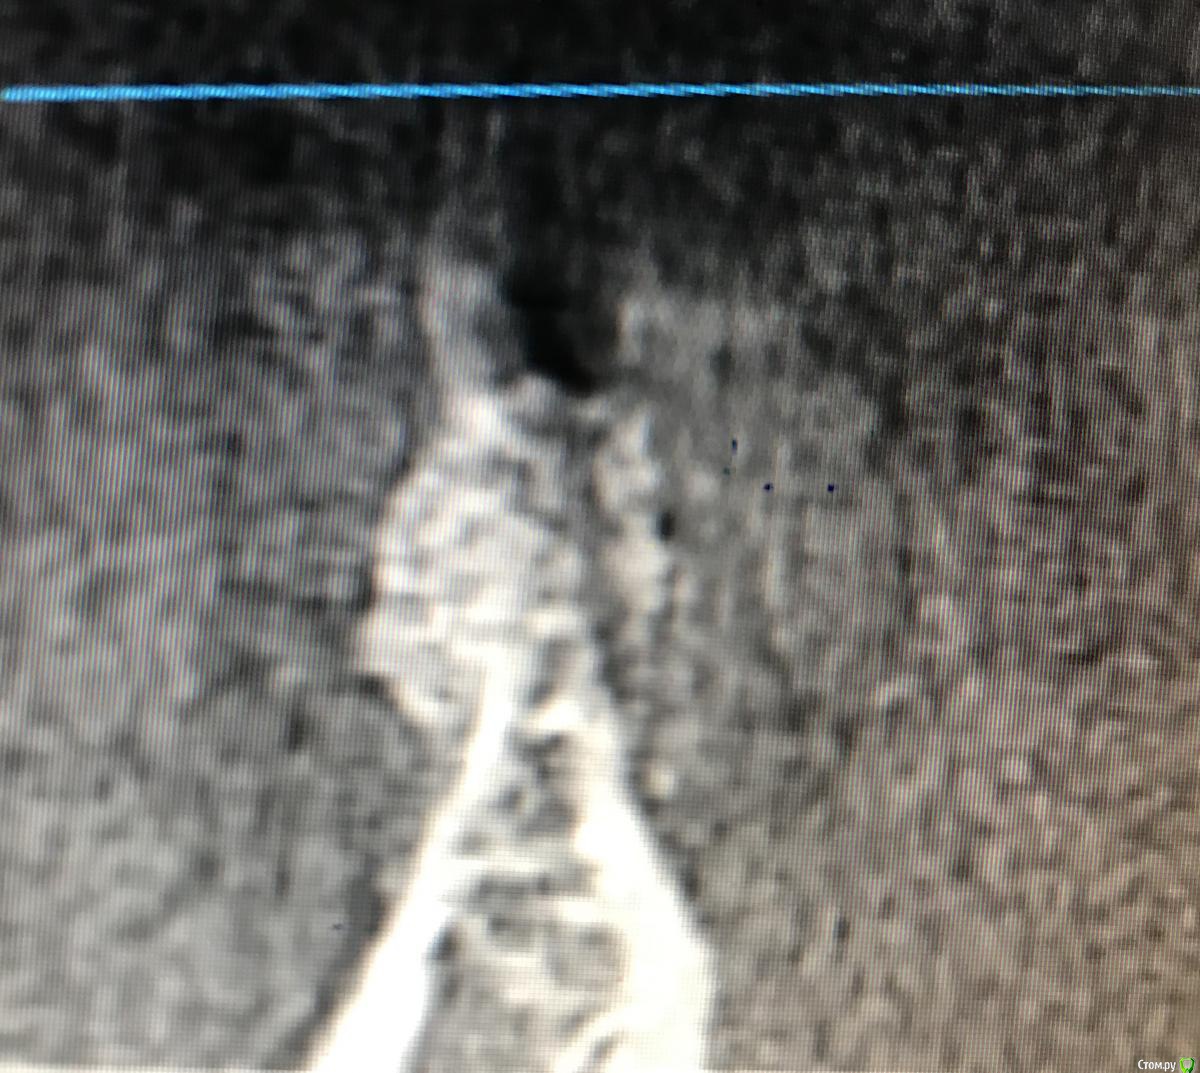

Kostoprav Опубликовано 21 декабря, 2018 Поделиться Опубликовано 21 декабря, 2018 Поделитесь опытом. Какой был графт,какой доступ,условия? На каком этапе заметили неудачу? С чем связываете? Какой срок наблюдения?графт остеобиол+ i prf . доступ аналогичный как у автора темы, использовал данную методику в боковых отделах нижней и верхней челюстях. из 6 пациентов только у двоих я получил прирост и то в одном случае результат был на троечку.неудачу замечал на этапе компьютерной томографии через 6 мес- отсутствие прироста кости либо графт просто "не прирастал" к кости ,а инкапсулировался в слизистой ( кт прилагается ). неудачи связываю с нестабильностью графта и возможно были повреждения периоста при его отслойке как следствие прорастание мягких тканей в графт. Ссылка на комментарий

колесников Опубликовано 22 декабря, 2018 Автор Поделиться Опубликовано 22 декабря, 2018 Я бы не назвал это неудачей,аугментат довольно плотно контактирует с кортикалкой. Мне кажется вы слишком низко отслоились,должна получится округлая сосиска. Я отслаиваю коронально,затем моделирую нужной формы. 1 Ссылка на комментарий

колесников Опубликовано 14 марта, 2019 Автор Поделиться Опубликовано 14 марта, 2019 (изменено) Это аллографт,не ксено. Если он интегрирован -он есть,если не интегрирован,не имеет контакта с нативной костью-он лизируется. Это ксерографт может инкапсулироваться и оставаться рентгеноконтрастным. Изменено 14 марта, 2019 пользователем колесников 1 Ссылка на комментарий